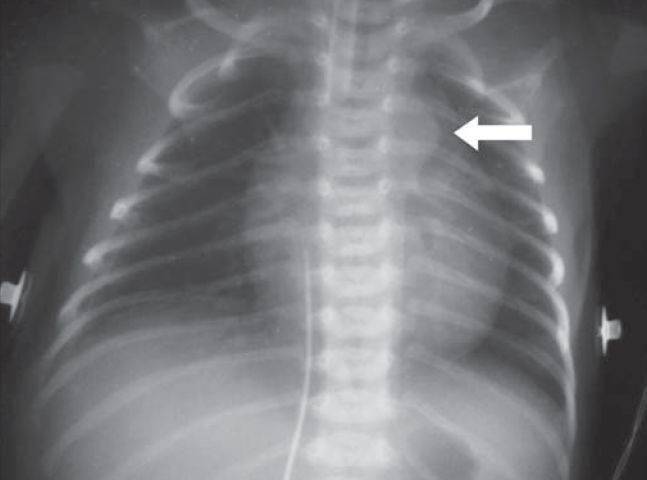

在胸片中,螺丝钉大头朝下卡在支气管里,需要通过支气管镜取出.

图片尺寸450x755